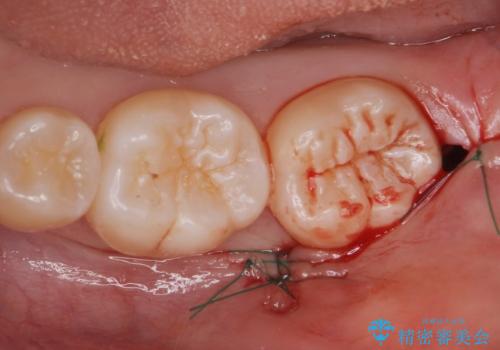

レントゲン、CTを撮影し安全を考慮して抜歯術を行いました。

抜歯後、1週間後に抜糸を行う必要があります。

無事に親知らず抜歯ができました。